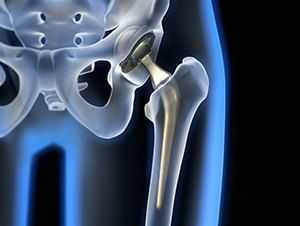

Рентгенологическая диагностика остеоартроза тазобедренных суставов

На точность оценки ширины суставной щели в тазобедренных суставах влияют 3 фактора: позиция больного, поворот конечности и правильная центрация рентгеновского луча при рентгенографии сустава. Сравнение ОА изменений в тазобедренных суставах у одних и тех же больных в 2-х положениях (стоя и лежа) показало, что в положении больного стоя ширина суставной щели была достоверно меньше, чем когда больной лежал на столе. Cуставная щель сужена в большей степени тогда, когда стопа направлена кнутри. Смещение рентгеновской трубки в сторону от центра сустава может достоверно изменить ширину суставной щели. При этом рекомендуется, чтобы центральный рентгеновский луч проходил через центр бедренной головки. Правда, необходимо отметить тот факт, что раздельная рентгенография тазобедренных суставов приводит к увеличению лучевой нагрузки на пациентов.

В начальных стадиях (1-2 стадии по Kellgren) ОА тазобедренных суставов при рентгенологическом исследовании определяются: незначительное сужение суставной щели, слабовыраженный субхондральный остеосклероз, точечные кальцификаты в области наружного края крыши вертлужной впадины (зачаток остеофитов), заострение краев ямки бедренной головки в области прикрепления круглой связки бедренной головки (рис. 1).

В поздних стадиях заболевания (соответствует 3-4 стадии ОА по Kellgren) отмечаются:

• прогрессирующее сужение суставной щели

• формирование различной формы и размеров остеофитов на краях суставных поверхностей вертлужной впадины, бедренной головки, отчего она со временем приобретает грибовидную форму. В средней части вертлужной впадины возможно формирование клиновидного остеофита, который может обусловить латеральное смещение бедренной головки

• углубление вертлужной впадины может быть связано с развитием остеофитов; протрузия ее возможна на фоне остеопороза или истончения костей, составляющих дно вертлужной впадины

• выраженный субхондральный остеосклероз. Проявляется в первую очередь в области крыши вертлужной впадины, затем в верхнем отделе бедренной головки

• в далеко зашедших случаях - уменьшение в объеме и уплощение суставной поверхности бедренной головки на фоне выраженной кистовидной перестройки костной ткани, чередующейся с участками субхондрального остеосклероза. Костные кисты могут быть единичными или множественными. Возникают они в верхней части вертлужной впадины или в зоне наибольшей нагрузки на суставную поверхность бедренной головки

• асептический некроз бедренной головки

• подвывихи бедренной кости чаще вверх и латерально, реже вверх и медиально

• уплотнение костной ткани и укорочение шейки бедренной кости.